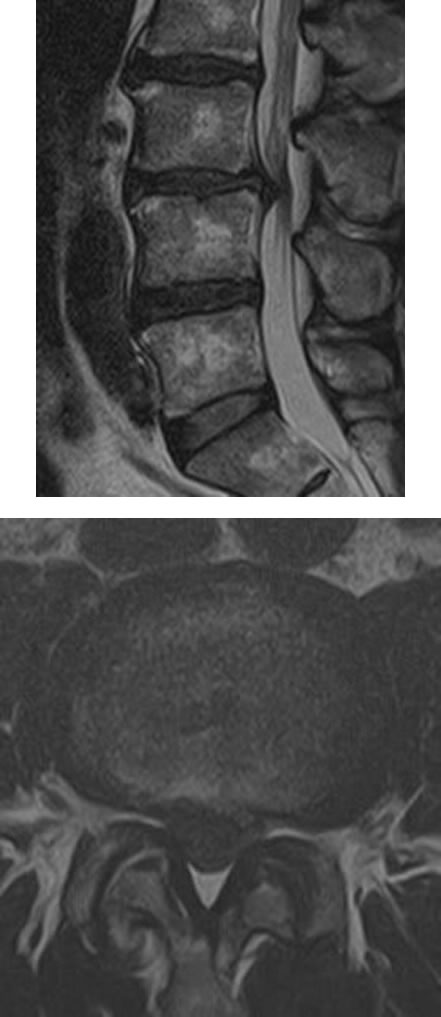

腰椎椎間板ヘルニアと腰部脊柱管狭窄症の違い

| 腰椎椎間板ヘルニア | |

|---|---|

| 椎間板のみが突出し、神経を圧迫した状態です。10~50 歳代に多いです。 | ![]() (腰椎を輪切り にした図) |